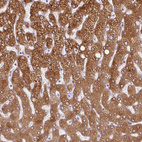

Immunohistochemistry analysis in human liver and pancreas tissues using HPA047729 antibody. Corresponding HSD11B1 RNA-seq data are presented for the same tissues.